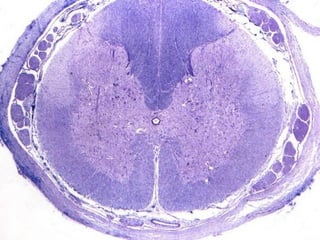

CASO CLINICO

(para primer año)

• MASCULINO DE 32 AÑOS QUE

PRESENTA DESDE HACE 5 MESES

CAMBIOS EN EL ESTADO MENTAL,

EPILEPSIA, CEFALEA Y MALESTAR

GENERAL.

• SE SOMETE AL PACIENTE A

RESONANCIA MAGNETICA

ENCONTRANDO LO SIGUIENTE:

• AL OBSERVAR EL TUMOR EN LA

IMAGEN SE DECIDE SOMETER AL

PACIENTE A UNA BIOPSIA DEL TUMOR

• SE ENCUENTRA LO SIGUIENTE

DIAGNOSTICO:

OLIGODENDROGLIOMA

PATOLOGICO

NORMAL